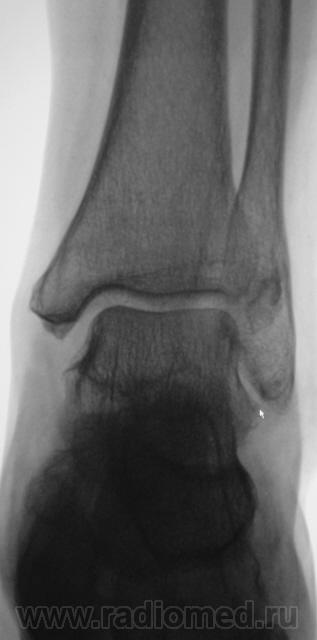

на консолидированный перелом Фолькмановского клина б\берцовой кости.

А, может быть, с учетом деформации малоберцовой кости, на боковой рентгенограмме, можно предположить, что, "это", откол фрагмента костной ткани от дистального эпифиза б/берцовой кости.

Если говорить о травме ( нужно учесть механизм), то можно предположить вдавленный перелом с огранич., но интенс. действием травмирующей силы с компрессией ( уплотнением) костной ткани.